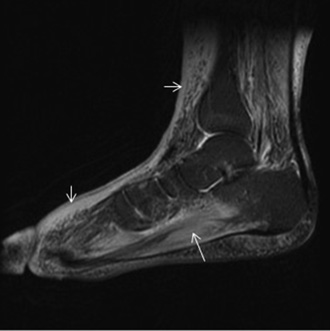

Resonancia Magnetica. Alteración de partes blandas en pie diabetico

Resonancia Magnética

La Resonancia Magnética puede, por sí sola, demostrar con alta certeza si el proceso de infección está limitado a los tejidos blandos o se extendió al hueso.

Los callos óseos plantares tienen una presentación característica por resonancia magnética. Cuando se detectan cambios en el brillo de las imágenes hay que sospechar una infección local. A veces el examen clínico del pie no puede identificar la profundidad del proceso infeccioso, y es allí cuando un examen de resonancia es de extrema utilidad.

Resonancia de ulceración en pie diabetico

La progresión de una úlcera infectada si no se trata en forma agresiva, puede dar lugar a una celulitis severa y complicarse con infección del hueso o de las articulaciones del pie.

Los tendones no son una vía común de diseminación de las infecciones. De tal manera puede encontraste en la Resonancia un engrosamiento y acumulación de líquido en las vainas de los tendones. Luego de administrar agente de contraste las membranas sinoviales inflamadas suelen realzar en forma evidente.

Cuando la osteomielitis (infección ósea) es de evolución crónica, suele ser un proceso más indolente que se manifiesta característicamente por heridas del pie diabético que no terminar de curar correctamente con los tratamientos comunes a través del tiempo.

En estos casos es indicativa la Resonancia Magnética porque puede demostrar con alta certeza si el proceso está limitado a los tejidos blandos o se extendió al hueso. En aquellos casos que requieren amputación como última salida terapéutica, la Resonancia es una herramienta imprescindible para la planificación quirúrgica, aclarando los límites de resección en la cirugía y facilitar el plan quirúrgico previo a una amputación para realizar una cirugía  lo más conservadora posible a la vez que exhaustiva.

Tenosinovitis infecciosa. Imagen de Resonancia Magnética